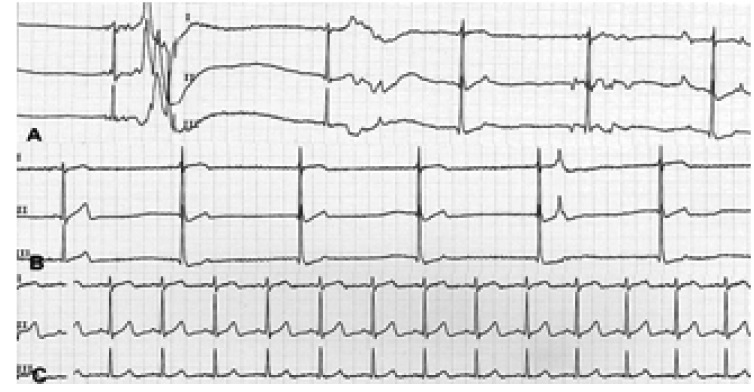

A 59-year-old man was admitted to hospital for the evaluation of syncope. The patient had been in good health except for when hypertension was detected 20 years earlier, and he had subsequently been treated for 3 years. Since he was about 30 years old, he had experienced many episodes of syncope when drinking a carbonated beverage (eg., a soda pop) and beer. About 4 years ago, syncope occurred while drinking cold water when he was taking a bath. Eating sticky foods such as a sweet potato, or even fast running caused syncope. The physical examination and routine laboratory results were normal except for a slightly increased serum creatinine level (132.6 µmol/L). Electrocardiography and chest X-ray findings were not specific. The left ventricular ejection ventricular hypertrophy was detected. A brain CT was normal. A carotid massage did not evoke any abnormal rhythms. Holter monitoring showed a sinus arrest with a maximum 7.2 seconds pause while drinking beer and a carbonated beverage (Figure 1A, 1B). An esophagogastroscopy, performed to search for an abnormality in the esophagus and stomach, showed only superficial gastritis at the fundus. Gastric distension by air could not induce syncope or an abnormal rhythm. An esophageal manometry showed no specific esophageal motility disorder except for transient low pressure in the lower portion of the esophagus. The patient was treated with a permanent pacemaker. After backing up the permanent pacemaker, esophageal balloon inflation by a Sengstaken-Blakemore tube with the pressure of 40 mmHg at the lower esophagus induced marked sinus bradycardia (Figure 2). However, no response was observed at the middle and upper esophagus.

A 59-year-old male was referred to hospital for the evaluation of about four episodes of syncope which he had experienced for 1 year. The first episode occurred with a loss of consciousness for 5 minutes following eating foods with feeling obstruction in the esophagus. No specific kinds or forms of foods had been associated with the symptom. He had experienced syncopal episodes usually right after eating, but sometimes while eating foods. The patient had been in good health except for having about ten episodes of an obstructive feeling while eating for 3 years. The result of an esophagogastroscopy conducted 1 year ago had been normal. Physical examination results showed no abnormality. The laboratory FT4: 26.445 pmol/L, TSH receptor antibody 30.5%). The blood count and liver function tests were normal. An electrocardiography showed sinus bradycardia (57 beats per minutes). A chest X-ray showed a compression fracture at the lower thoracic spine. A thyroid scan showed no demonstrable abnormal finding. The Holter monitoring test could not be done for refusal of patient and rarity of the symptoms. Inflation of the balloon in the lower esophagus and gastroesophageal junction that was at the 9th thoracic spine level resulted in junctional rhythm (32~36 beats per minutes) with lightheadedness (Figure 3, Figure 4). However, an atropine pretreatment blocked this response (Figure 3C). A syncopal episode was considered to occur with eating a bolus of food in a hurry; thus, he was treated by changing his eating habits for syncope and given propylthiouracil for Graves' disease.